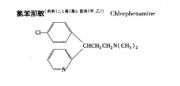

| 2021年7月26日 (一) 20:01 | 氯苯那敏结构式.jpg (文件) |  |

14 KB | 77921020 | Uploaded with SimpleBatchUpload | 3 |